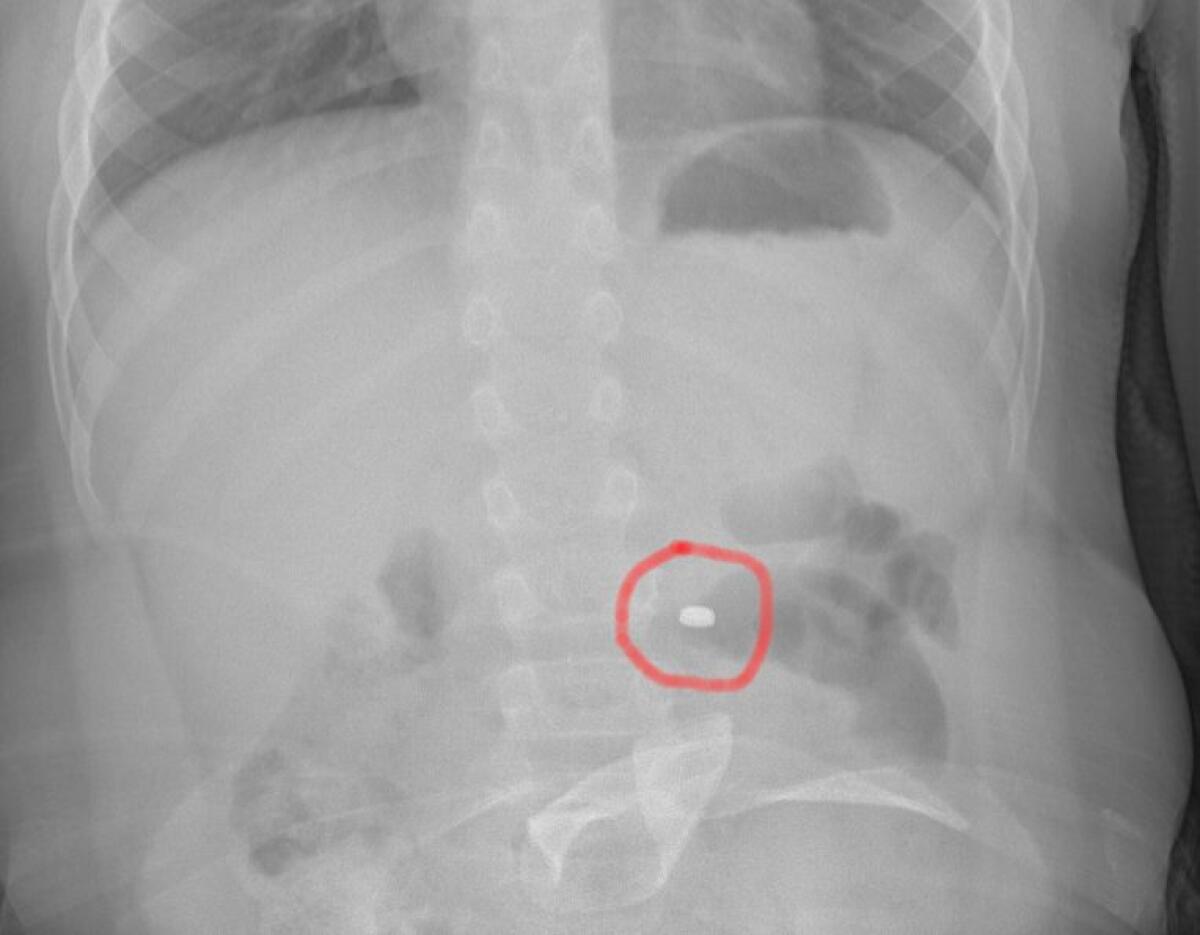

La famiglia, naturalmente spaventata, dopo una prima valutazione al PS della propria città, è stata indirizzata all’Ospedale Cannizzaro di Catania. Qui i medici hanno compreso il pericolo e applicato le linee guida riferite precisamente all’ingestione di una pila a bottone. Eseguita la radiografia dell’addome che ha messo in evidenza la presenza e la localizzazione del corpo estraneo, il bambino è stato condotto in sala operatoria dove gli endoscopisti, con l’assistenza degli anestesisti, hanno potuto estrarre in sicurezza il piccolo oggetto, prima che esso potesse causare conseguenze più importanti. Dopo una notte in osservazione, tornato in piena salute, il bimbo ha fatto rientro a casa con i genitori.